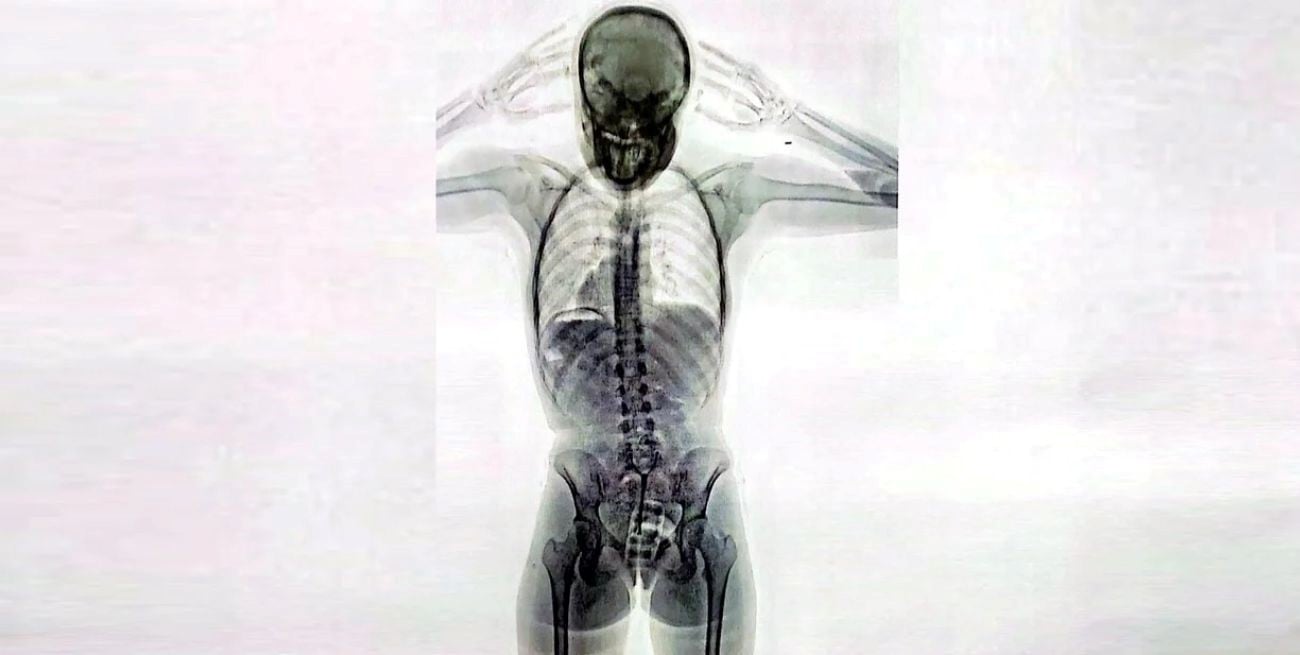

Una joven de 20 años fue detenida en los últimos días en el Aeropuerto Internacional de Ezeiza tras ser descubierta por las autoridades aeroportuarias cuando intentaba viajar a Europa con droga oculta dentro de su cuerpo. Las imágenes del escáner de rayos X revelaron la presencia de más de 700 gramos de cocaína en su vagina y su estómago.

Impresionante imagen de un escáner de rayos X: una mula tenía 78 cápsulas de cocaína en el cuerpo

Ante consultas por parte de inspectores de la Aduana, la pasajera “respondió de manera incongruente y dubitativa”, lo cual levantó aún más las sospechas. Ante esta situación, agentes de la Policía de Seguridad Aeroportuaria (PSA), conjuntamente con funcionarios de la Dirección General de Aduanas y personal de AIRCOP, procedieron a realizarle un control corporal no invasivo mediante equipo de rayos X (Body Scan) y delante de la presencia de testigos.

La inspección dio pie a la revelación del delito: en las imágenes los efectivos observaron la posible presencia de elementos extraños en el organismo, concentrados en su zona genital.